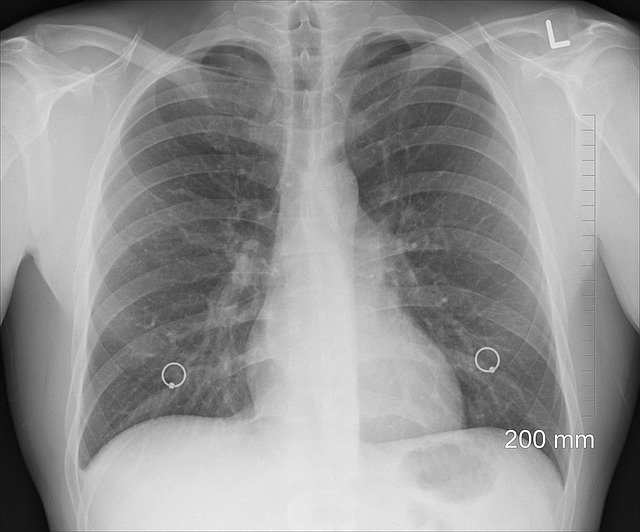

코로나와 폐렴의 차이를 본격적으로 말씀드려보겠습니다. 일단 비슷한 점은 코로나와 감기, 폐렴이 증세가 큰 차이가 없다는 점입니다. 폐렴은 발열, 가래, 기침, 호흡의 곤란 등을 일반적으로 보이는데, 코로나 19는 37.5도 이상의 발열, 기침, 인후통, 호흡곤란, 가래, 두통, 설사 등의 유증상 혹은 무증상으로 발현된다고 하죠.

코로나 19는 정체가 밝혀지지 않은 바이러스가 원인이고 폐렴의 경우는 세균, 바이러스, 곰팡이처럼 다양한 원인으로 폐에 염증을 일으키는데 전염성은 그 원인이 무엇인가에 따라 다를 수 있다고 합니다.